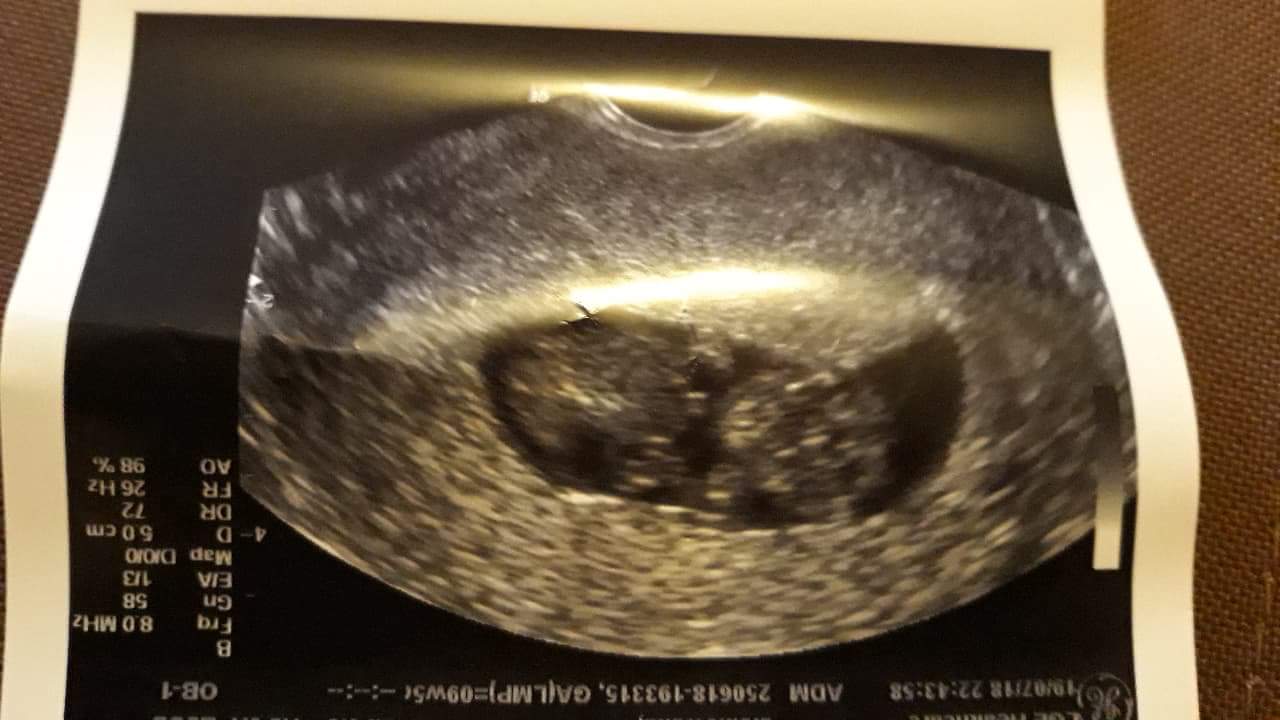

Z bejbikiem wszystko w porzadku pieknie rosnie ma kuz 3.08cm pieknie pyka mu serduszko

I mamy nakaz lezenia bo jest krwiak 2x1 przy kosmowce za tydzien kontrola czy sie zmniejsza

A tu nasza fasolkakosmita

Zobacz załącznik 879278 Zobacz załącznik 879279